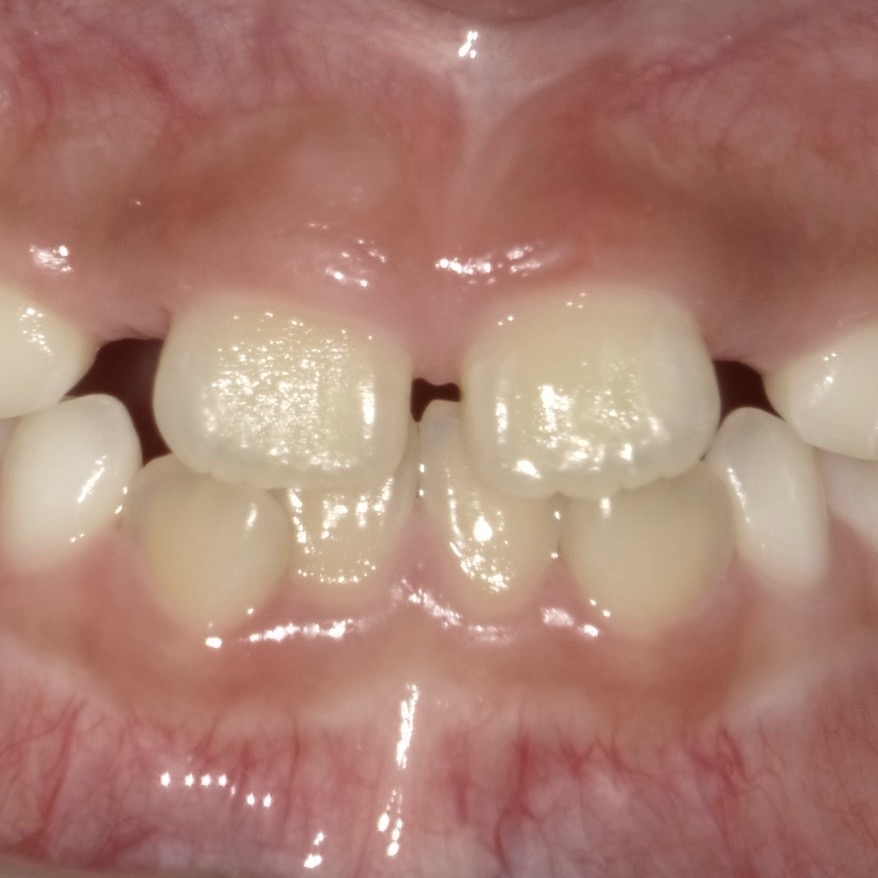

正中離解とは、中央に生えている2本の前歯(中切歯)の間に隙間が空いている状態を表します。

例えば、この写真のような状態です。